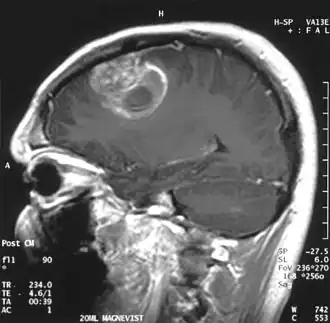

- Standardverfahren ist die Magnetresonanztomographie (MRT), auch Kernspintomographie genannt, ein diagnostisches Schnittbildverfahren zur Darstellung von Organen und Geweben mit Hilfe von Magnetfeldern. Sie basiert auf der Gewebestruktur und dem Wassergehalt und hat eine sehr hohe Erkennungsrate für Hirntumoren, ohne ionisierende Strahlung einzusetzen. Kontrastmittel ist nicht immer erforderlich. Die Magnetresonanzspektroskopie (MRS) ist ein in spezialisierten Zentren verfügbares Zusatzverfahren, um aus tumorverdächtigen Arealen ein Signalspektrum aufzunehmen und damit ihre chemische Zusammensetzung abzuschätzen.